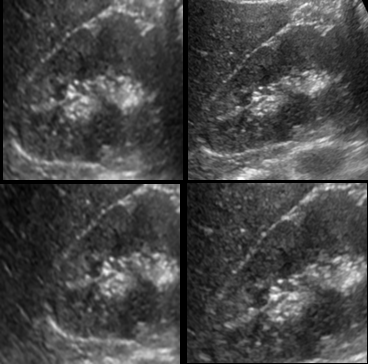

Fig. 3LABEL:sub@subfig:a and LABEL:sub@subfig:b shows a case in which the baseline method was affected by the presence of diaphragm, kidney and liver boundaries creating a texture similar to renal-sinus portion, while CaffeNet had excellent localization. Fig. 3LABEL:sub@subfig:c and LABEL:sub@subfig:d illustrate a case where CaffeNet resulted in over-segmentation containing the diaphragm, clearly illustrating that in limited data problems careful feature-engineering incorporating domain knowledge still carries a lot of relevance. Finally, we achieved a best performance of 86% average detection accuracy using the hybrid approach (Section 3.5). More importantly, the number of failures of the hybrid approach was 3/45, which is 20% better than either of the methods.

Refer to caption

(a) Haar

(b) CaffeNet_FA

(c) Haar

(d) CaffeNet_FA

Figure 3: Visual comparison of Baseline Method with CaffeNet Transfer